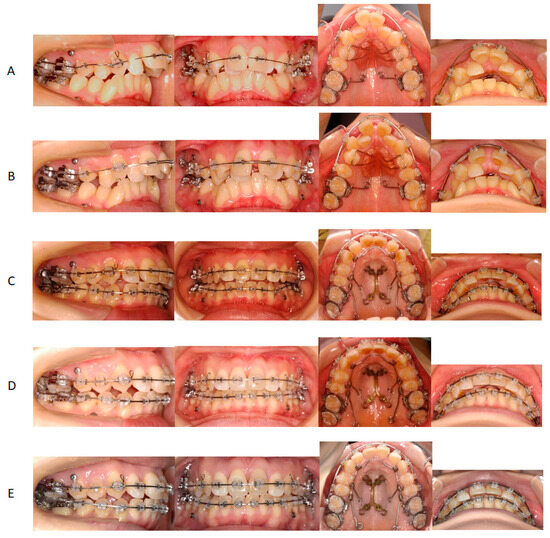

2. Detailed Case Description

2.3. Treatment Progress